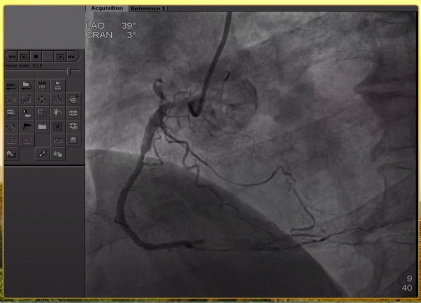

造影结果

左主干偏心斑块,重度狭窄;前降支中段重度狭窄;回旋支开口扭曲伴重度狭窄,支架远端完全闭塞,高位钝缘支开口重度狭窄;右冠开口次全闭塞,开口处可见支架影,中段支架远端完全闭塞。

前降支、回旋支造影结果